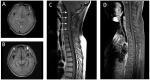

Autoimmune glial fibrillary acidic protein astrocytopathy is a novel form of autoimmune meningoencephalitis related to GFAP autoantibodies. This condition is still being characterized, and few pediatric patients have been identified. Here, we report three patients presenting with fever, nausea, and headache, following progressive disturbance of consciousness, limb weakness, dyspnea, or urine retention. MRI analysis revealed that T2-hyperintense lesions, or enhancement of the meninges and spinal cord. CSF and serum analyses revealed they were positive for GFAP antibody, confirming GFAP astrocytopathy diagnosis. Treating the patients with IVIG, with or without intravenous steroids, gradually improved their clinical symptoms. Our findings indicate that GFAP astrocytopathy should be considered in children who are clinically diagnosed with meningoencephalitis, whether or not myelitis is present, and if the MRI reveals enhancement of meninges or spinal cord, T2-hyperintense lesions, or a pattern of linear perivascular gadolinium enhancement. Suspected cases should be tested for GFAP antibody as soon as possible because these patients may benefit from immunotherapy.